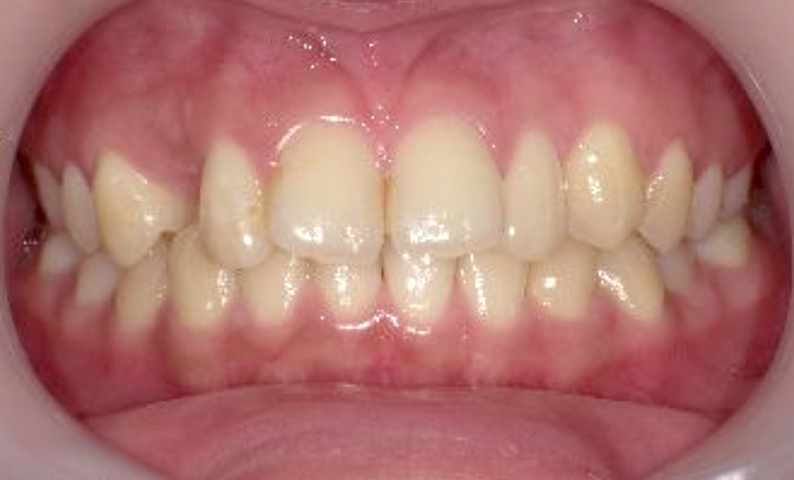

症例_025 上顎だけの部分矯正

治療期間:7ヶ月金額:30万円+税女性前歯のガタガタ上の前歯だけ

| Before | After |